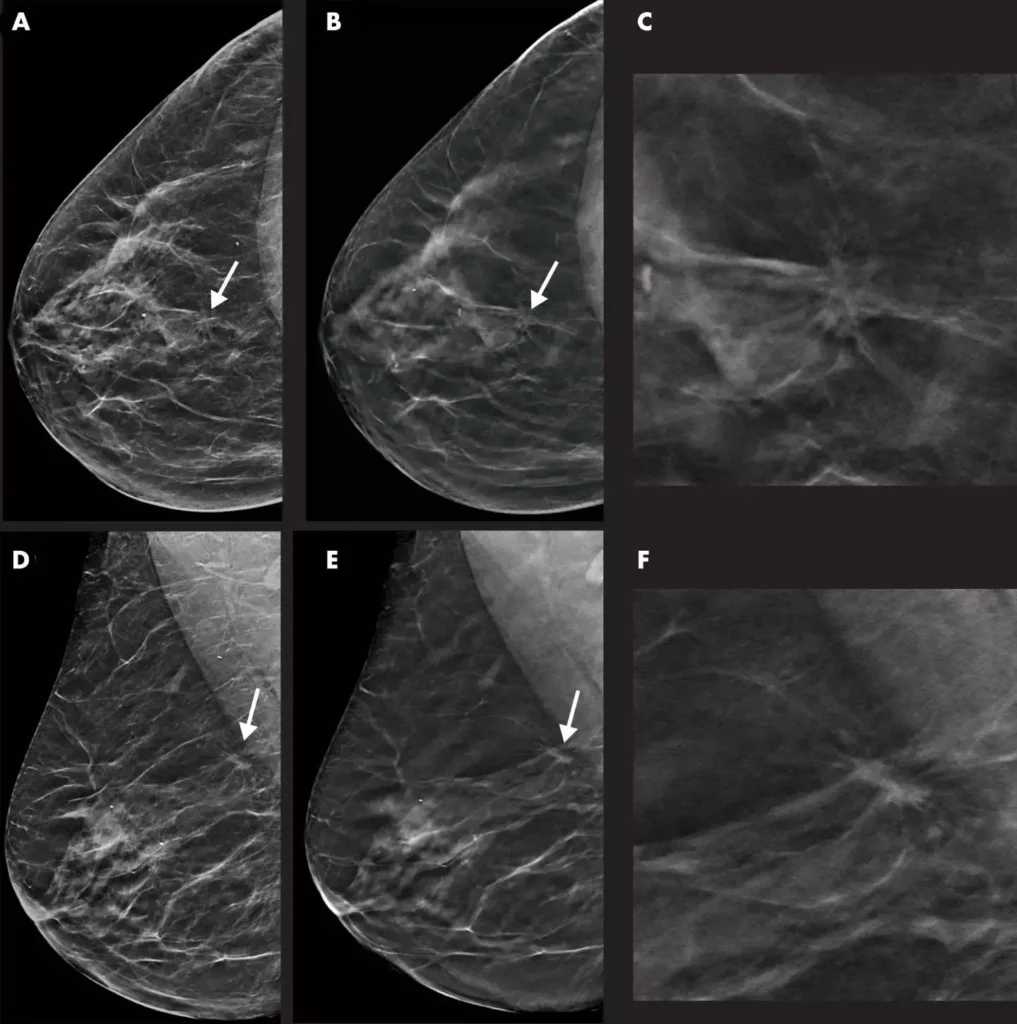

Mammography

img01

DBT (Digital Breast Tomosynthesis)

• More Accurate Breast Screening

3D mammography captures the breast from multiple angles and reconstructs it into a detailed 3D image. This helps doctors see through overlapping tissue and detect abnormalities earlier.

• Clearer Results, Fewer Callbacks

High-resolution images with strong contrast make it easier to find small lesions reducing the chance of needing repeat scans.

• Better Detection in Dense Breasts

3D mammography is especially helpful for women with dense breast tissue, where traditional 2D scans may miss small findings.

• Safer, Lower Radiation 2D Images

Our system uses Synthesized 2D, meaning it creates the 2D image directly from the 3D scan — no extra exposure and no second compression.

• Accurate Localization for Your Doctor

The 3D view provides exact information on the size, shape, and location of any lesion, helping your doctor plan the right care.